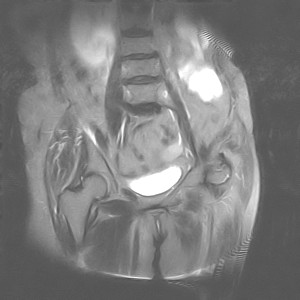

图像太差了 1、右侧臀肌旁脓肿? 建议增强 2、左侧股骨头坏死并半脱位

1、左侧股骨头坏死并髋关节半脱位;

2、右侧臀肌感染,(可能褥疮所致)